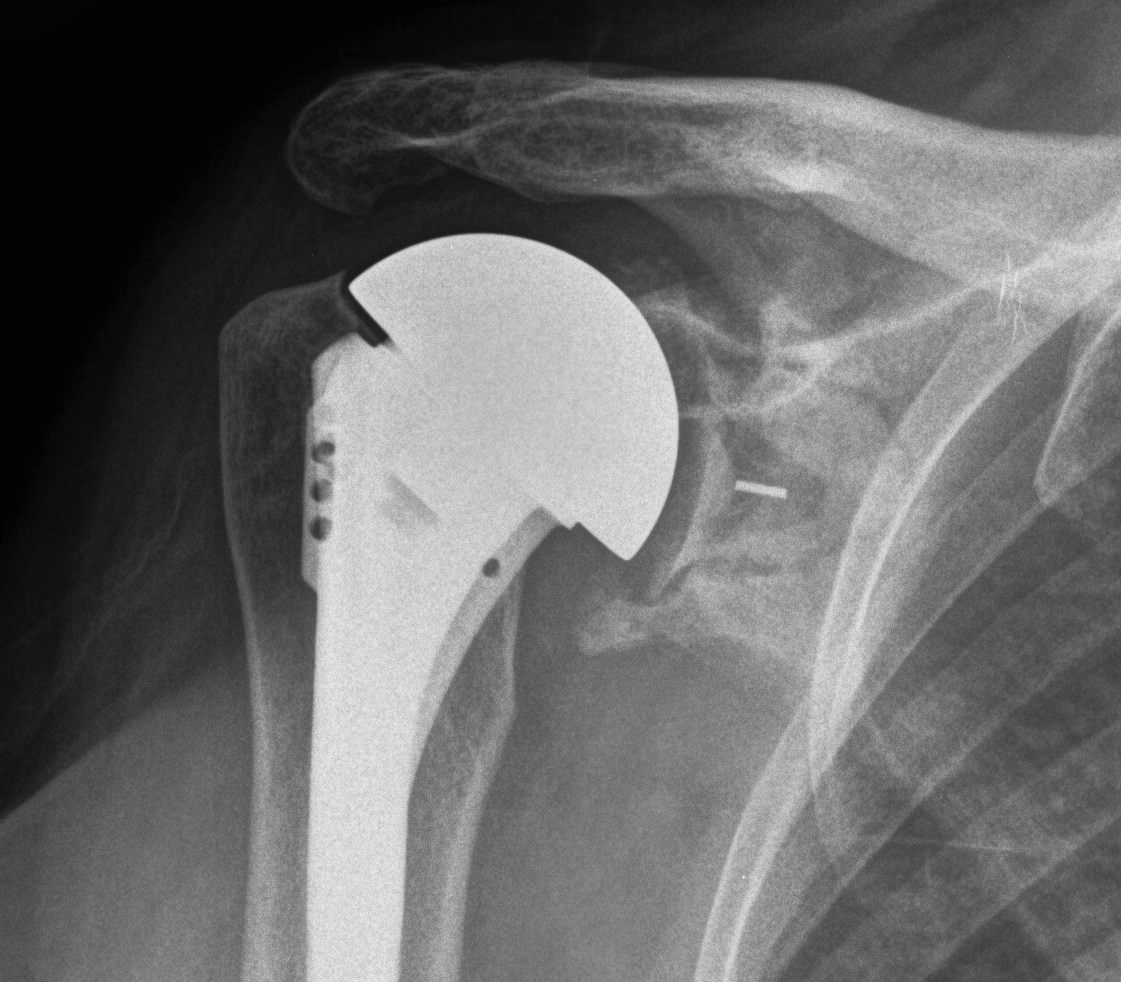

TSR Periprosthetic FractureTSR Periprosthetic Fracture

aTSA fracture 1aTSA fracture 2revTSA following fracturerevTSA for fracture